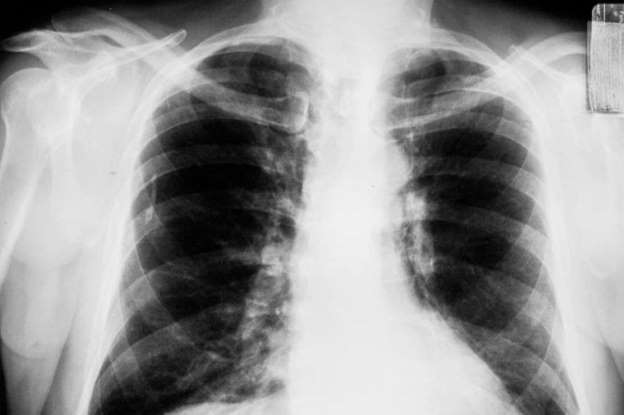

A young 31 year old woman was diagnosed with lung cancer, and has never smoked a day in her life. She was an athlete with a daily work out routine until one day she noticed she was having discomfort and her work outs were becoming harder to complete. Doctors told her she is just working too hard and to take things easy, but she knew it was something more than that. After a CT scan, she was diagnosed with lung cancer. What she did not realize was that her home was exposed to radon, a gas seeping from the soil and causing her cancer. click here